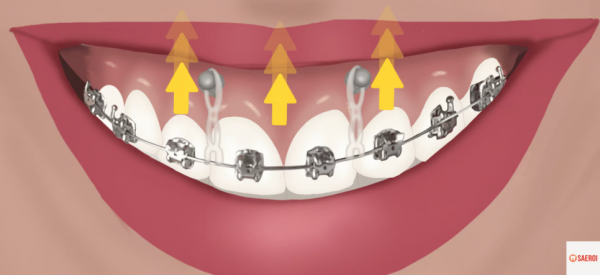

(3) 치아교정

예전에는 양악수술로만 치료 가능하던 케이스들도

미니스크류와 같은 최신 치아교정 기법들이 생겨나면서

교정치료만으로 개선이 가능하게 되었습니다.

아래로 많이 내려와 보이는 앞니들을

치아교정을 통하여 위로 올려주게 된다면

웃을 때 잇몸보다는 치아가 더 많이 보이게 되겠죠?